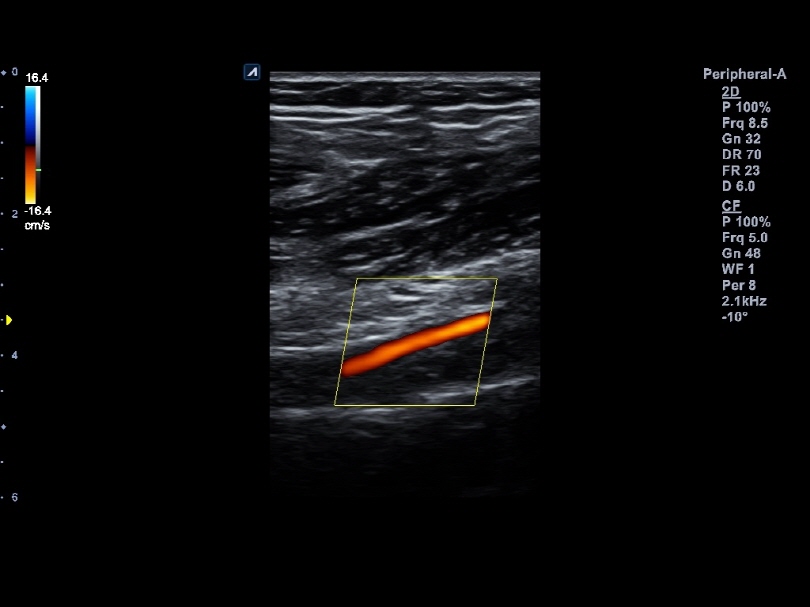

L8-17H

High density linear transducer(8-17MHz)

Application:

Breast, EM, MSK, Vascular, Small Parts

L3-12H

High density linear transducer (3-12MHz)

Application:

Breast, EM, MSK, Vascular, Small Parts

L3-12HWD

High density wide footprint linear transducer (3-12MHz)

Application:

Breast, EM, MSK, Vascular, Small Parts, Appendix

L3-12T

Linear transducer (3-12MHz)

Application:

Breast, EM, MSK, Vascular, Small Parts, Appendix